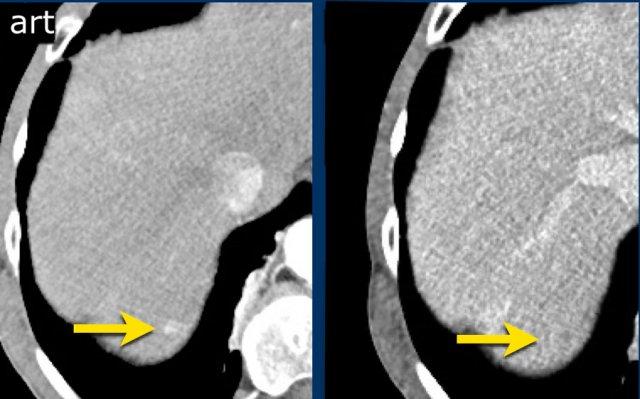

LI-RADS 3

Hình ảnh thì động mạch, thì tĩnh mạch cửa và thì muộn của một tổn thương LIRADS 3.

Tại phân thùy 5 có một tổn thương dưới bao gan với ngấm thuốc động mạch mạnh mà không có thải thuốc ở thì tĩnh mạch cửa hoặc thì muộn.